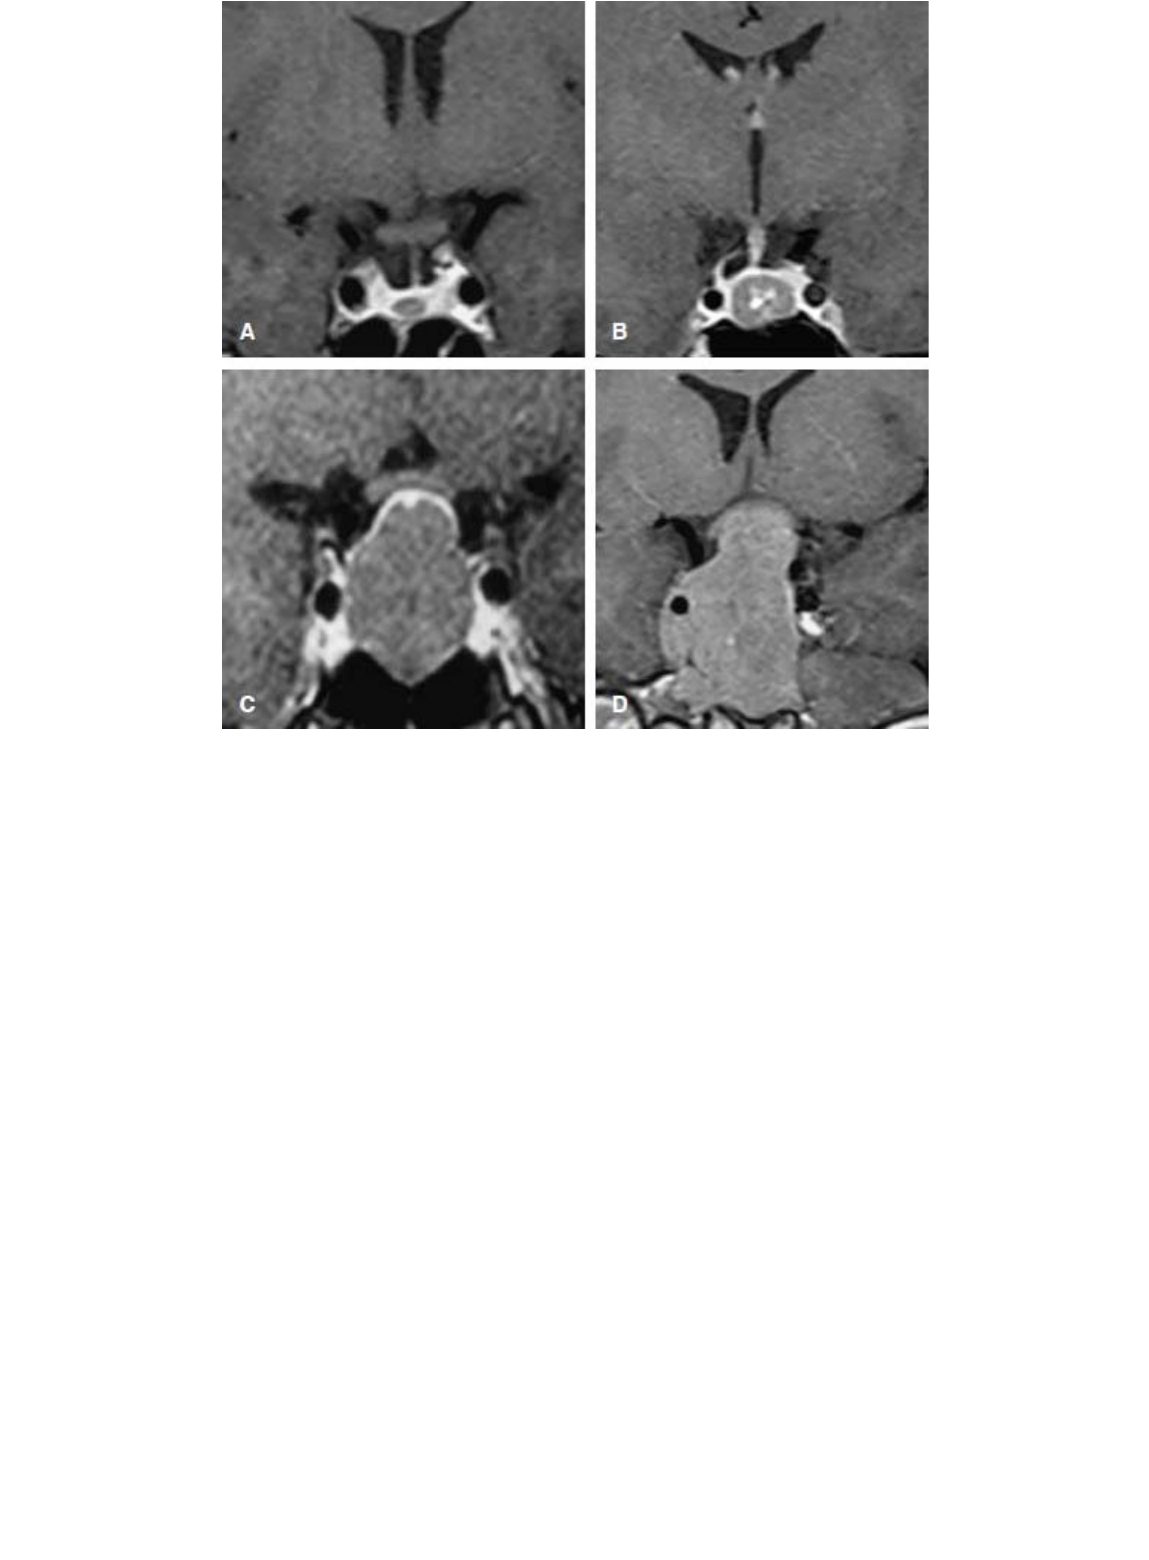

Figura 7.1 Exemplos de ressonância magnética de sela túrcica pré-operatória de pacientes com acromegalia curados com

tratamento primário cirúrgico (corte coronal, sequência pesada em T1, após administração de gadolínio). A. Microadenoma

intrasselar. B. Macroadenoma intrasselar. C. Macroadenoma com expansão infrasselar e suprasselar com rechaço superior

do quiasma óptico. D. Macroadenoma com expansão infrasselar e suprasselar com compressão de quiasma óptico e

parasselar direita (a possível invasão de seio cavernoso à direita não se confirmou durante o procedimento cirúrgico).